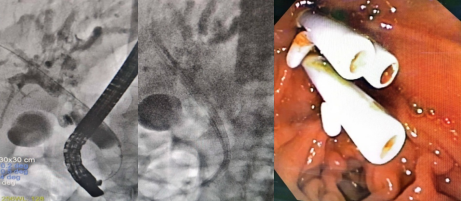

急性梗阻性化脓性胆管炎是发展最快的急腹症之一。手术尚未开始,患者血压下降、心率减慢,休克体征突显,甚至一过性出现心跳骤停。外二科主任喻定刚、ICU主任张泽奎、麻醉科主任雍记智与杨林主任医师再次床旁MDT讨论,共同制定治疗方案。明确了呼吸循环支撑下的ERCP手术是最大获益策略。杨林主任医师再次向家属沟通,说明病情的危重性和手术的必要性,获得了家属的充分理解和信任。待患者生命体征平稳后,于2021年12月26日16:03开始行ERCP术,于16:40分顺利结束。经过30余分钟紧张、短暂的超级微创手术治疗,不仅取出胆总管大部分结石,还安置了鼻胆管引流(ENBD)减轻胆总管压力,使患者暂时度过了生死第一关。术后经鼻胆管引流管道抽取胆汁见多量黄白色絮状物,送微生物培养培养出大肠埃希菌,患者转入ICU加强治疗。经上述综合性治疗后,患者生命体征平稳,感染指标、黄疸明显好转。于2021年12月09日再次行ERCP,此次治疗目的以安置胆总管支架内引流和扩张肝总管狭窄为主。术中发现肝管汇合处狭窄,胆总管及左肝管内多发结石。经过取石网篮、取石球囊反复取出多发结石及胆泥,扩张肝总管后安置了3枚胆总管支架。后期复查血常规正常。肝功能稳步改善。患者于12月14日顺利出院。